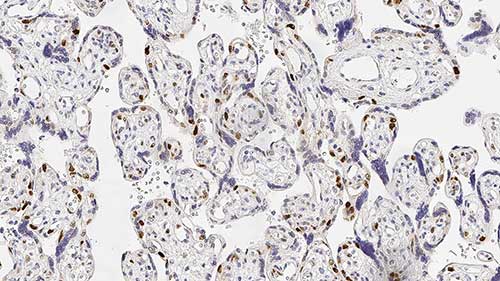

Transverse section of skeletal muscle fibers. Immunohistochemical staining for Alpha Sarcoglycan. Note the demonstration of localized Alpha Sarcoglycan to the sarcolemma of the muscle fibers. Alpha Sarcoglycan: clone Ad1/20A6

In normal skeletal muscle, dystrophin, the protein product of the gene which is defective in Duchenne and Becker muscular dystrophy, is attached to the muscle membrane via a complex of proteins (dystrophin-associated glycoproteins, DAGs). Dystrophin-deficient muscle shows a generalized reduction in DAG labeling. The expression of different members of the dystrophin glycoprotein complex is altered in several types of muscular dystrophy. For example, patients with LGMD2D have mutations in the gene for alpha-sarcoglycan, those with LGM2E have mutations in the beta-sarcoglycan gene, those with LGM2C have mutations in the gamma-sarcoglycan gene and those with LGM2F have mutations in the delta-sarcoglycan gene. As the sarcoglycans function together as a sub-complex, mutations in any one of the sarcoglycan genes usually results in variable expression for the whole group.

Sarcoglycan Antibodies are recommended for the detection of specific antigens of interest in normal and abnormal tissues, as an adjunct to conventional histopathology using non-immunologic histochemical stains.